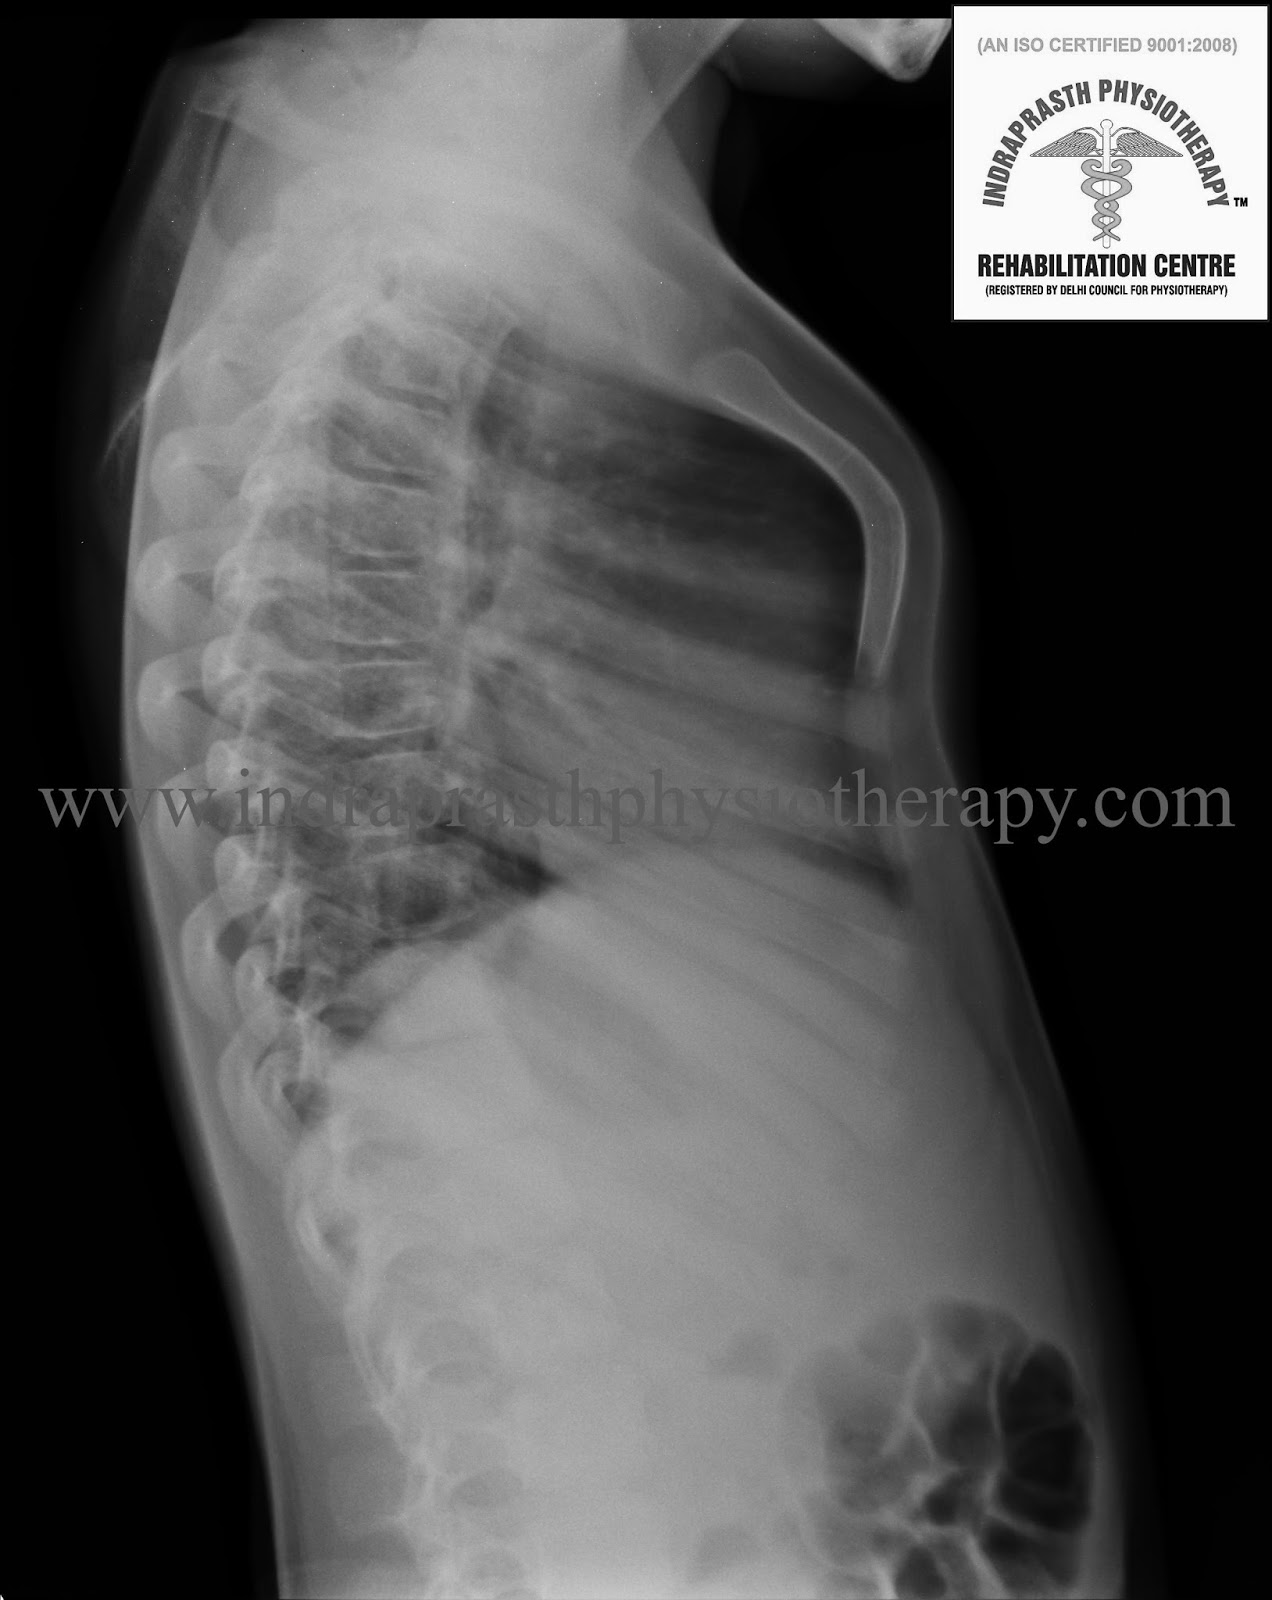

From indraprasthphysiotherapy.blogspot.com

INDRAPRASTH PHYSIOTHERAPY CENTRE PIGEON CHEST (PECTUS CARINATUM) Pigeon Chest What Is It It’s marked by an abnormally outward. pectus carinatum (pigeon chest): pectus carinatum (pigeon chest) causes, symptoms and treatment. It happens when part of the. pectus carinatum, also known as pigeon breast or pigeon chest, causes your breastbone and ribs to push outward. pectus carinatum or pigeon chest, is a genetic disorder that makes the chest wall. Pigeon Chest What Is It.